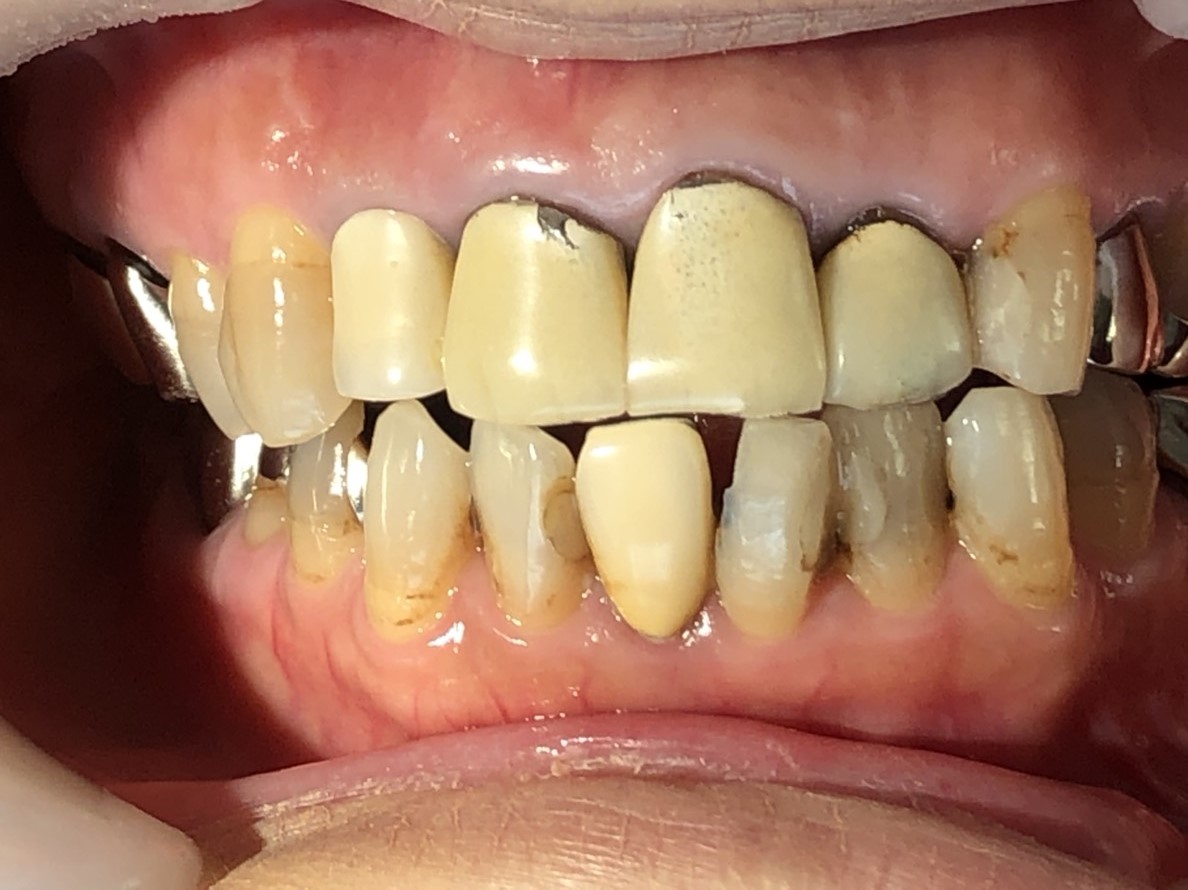

歯周病治療から始まり、根管治療を終え審美歯科治療の途中経過です。

患者さんは前歯だけを綺麗にしたいと来院されたのですが、他の奥歯も続けて治療希望したので、引き続き治療を進めています。

私のクリニックでは所沢、飯能、狭山、瑞穂、青梅、東京都内から、きれいな歯、エステティックすなわち見た目、審美が気になり治療を希望した患者さんにはただ見た目ではなく、見えない部分(根の状態等)も大事だと説明し、そこからスタートします。古い薬が入っているので根の治療は必ず行います。歯茎が下がり被せ物との隙間があると、歯槽膿漏が進行しているケースが殆どです。今回、下の前歯2本と上の前歯4本をやり直したいとの事でしたがレントゲンの結果、昔の古い金属の深い土台が入っていました。根を折らずにこの長く深い土台を除去する事は技術的に困難でリスクを伴ないましたが、本人の希望もあり出来る事は全てし、歯を折らずに根の治療を終える事が出来ました。これも経験があった上の自信ですから、患者さんの要望に答える事が出来ました。間違ってはならない事は、決して勘で治療してはいけません!なぜならば、医療は科学だからです。(これは研修医時代の恩師の教えでもあります)

写真の患者さんは6カ月以上前に来院された時の写真です。半年かけたお陰で、始めて良い治療ができるんです。それくらいかけて徐々に歯ぐきを良くしていくのです。